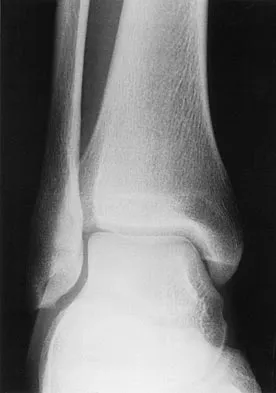

A soccer player who sustained a twisting injury to the right ankle while making a cut is unable to bear weight and has diffuse tenderness over the anterior and lateral aspects of the ankle. Examination also shows a positive squeeze test. Plain radiographs and a stress radiograph are shown in Figures 26a through 26c. Radiographs of the leg and knee are normal. What is the most appropriate management?

Explanation

The mechanism of injury, physical examination, and radiographs indicate a "high" ankle sprain with disruption of the distal tibiofibular ligaments and interosseous membrane. These injuries typically involve pronation and external rotation forces. In addition, recovery is significantly delayed, often requiring 6 to 8 weeks to heal. Radiographs obtained months after recovery often show calcification within the distal syndesmosis, which is not typically symptomatic. This patient has gross instability, resulting in a high incidence of chronic diastasis and subluxation leading to impaired function. Treatment should consist of reduction and stabilization with a transsyndesmotic screw because this injury demonstrates a widened syndesmosis. Boytim MJ, Fisher DA, Neumann L: Syndesmotic ankle sprains. Am J Sports Med 1991;19:294-298.